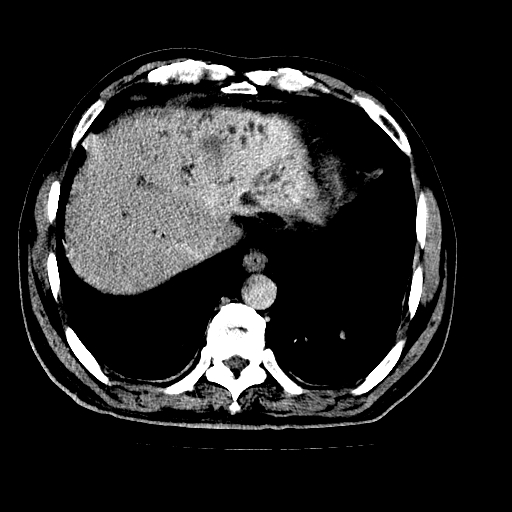

男,66岁,上腹部不适、黄染一周。彩超示:肝左叶占位,肝内胆管扩张,胆总管扩张,胆总管占位?

肝左叶不规则软组织肿块影,边缘不规整邻近肝实质受累分界不清;肝内胆管(左叶)明显扩张成“软藤状”,诊断:肝左叶胆管细胞癌。

肝左叶占位性病变,并胆管扩张,符合胆管细胞癌ct表现,门脉左支受累,左肾囊肿。窗宽太窄了,其他的看不清

左叶胆管细胞癌累及胆总管,门脉左支受侵,慢性胆囊炎胆结石,左肾小囊肿